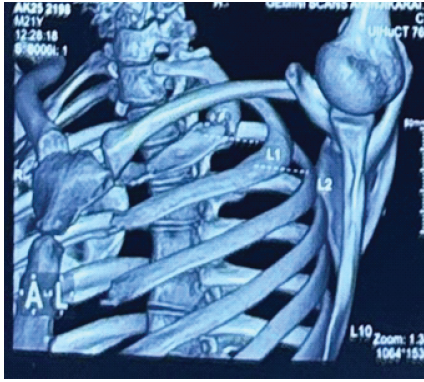

Computed tomography (CT) chest revealed cortical discontinuity of the lateral first rib with mixed lytic–sclerotic changes, subtle periosteal reaction, and mild soft-tissue inflammation. The lesion was seen indenting the divisions of the left brachial plexus and closely abutting the left subclavian artery (Fig. 1 and 2).

Figure 2: Three dimensional computed tomography reconstruction of the chest showing the location of the first rib fracture and reduced costoclavicular space, causing potential compression of the brachial plexus.